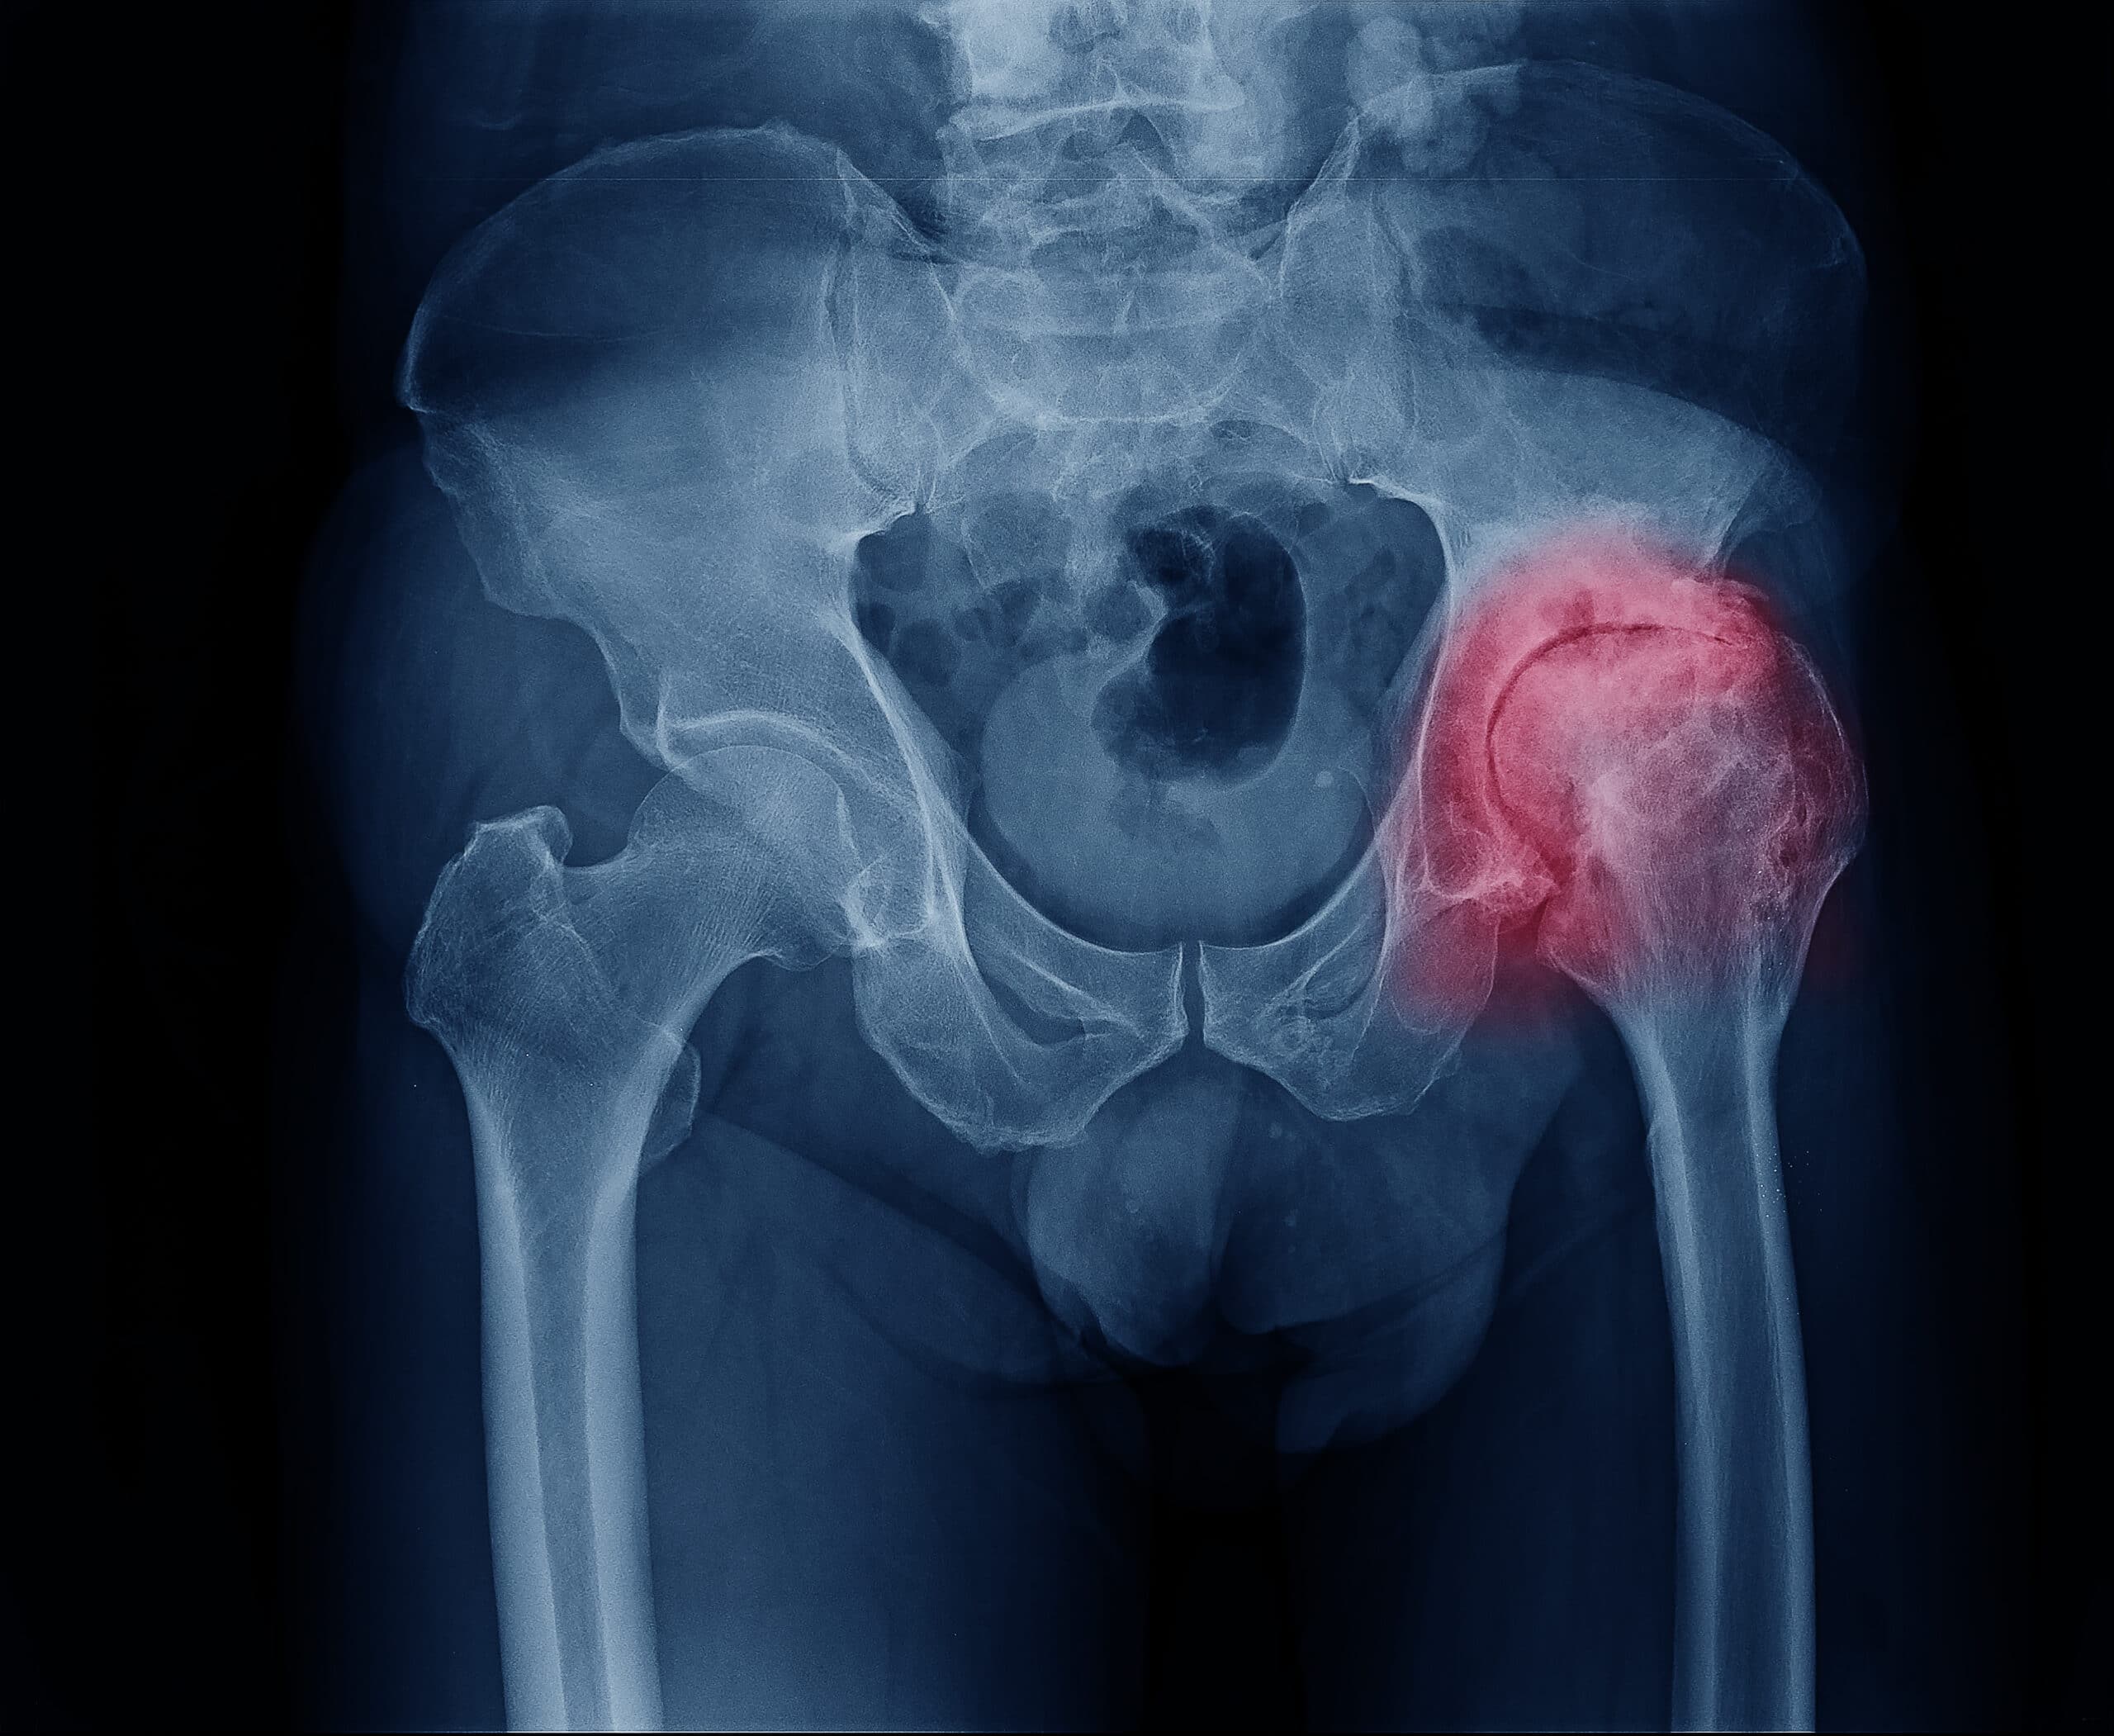

Hip Fracture

Hip Osteoarthritis